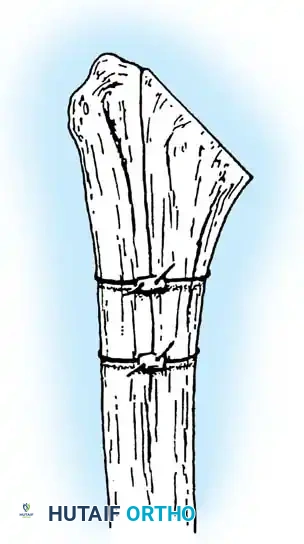

3. Humeral Head Resection

Dislocate the humeral head anteriorly through external rotation and extension. Remove peripheral osteophytes to identify the true anatomical neck. The humeral cut is made along the anatomical neck, typically at 30 degrees of retroversion and 45 degrees of inclination.